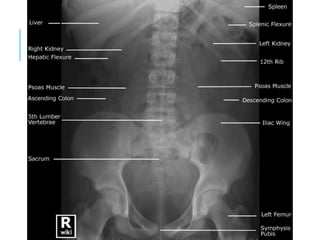

RADIOLOGY OF

ABDOMEN

ABDOMINAL X-

RAY

AP

PA